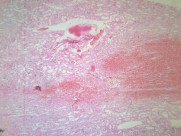

肾小管坏死(12)张

为急肾衰最常见类型,约占75%~80%.它是由于各种病因引起肾缺血及/或肾毒性损害导致肾功能急骤、进行性减退而出现的临床综合征.主要表现为肾小球滤过率明显降低所致的进行性氮质血症,以及肾小管重吸收和排泄功能低下所致的水、电解质和酸碱平衡失调.据尿量减少与否分少尿(无尿)…